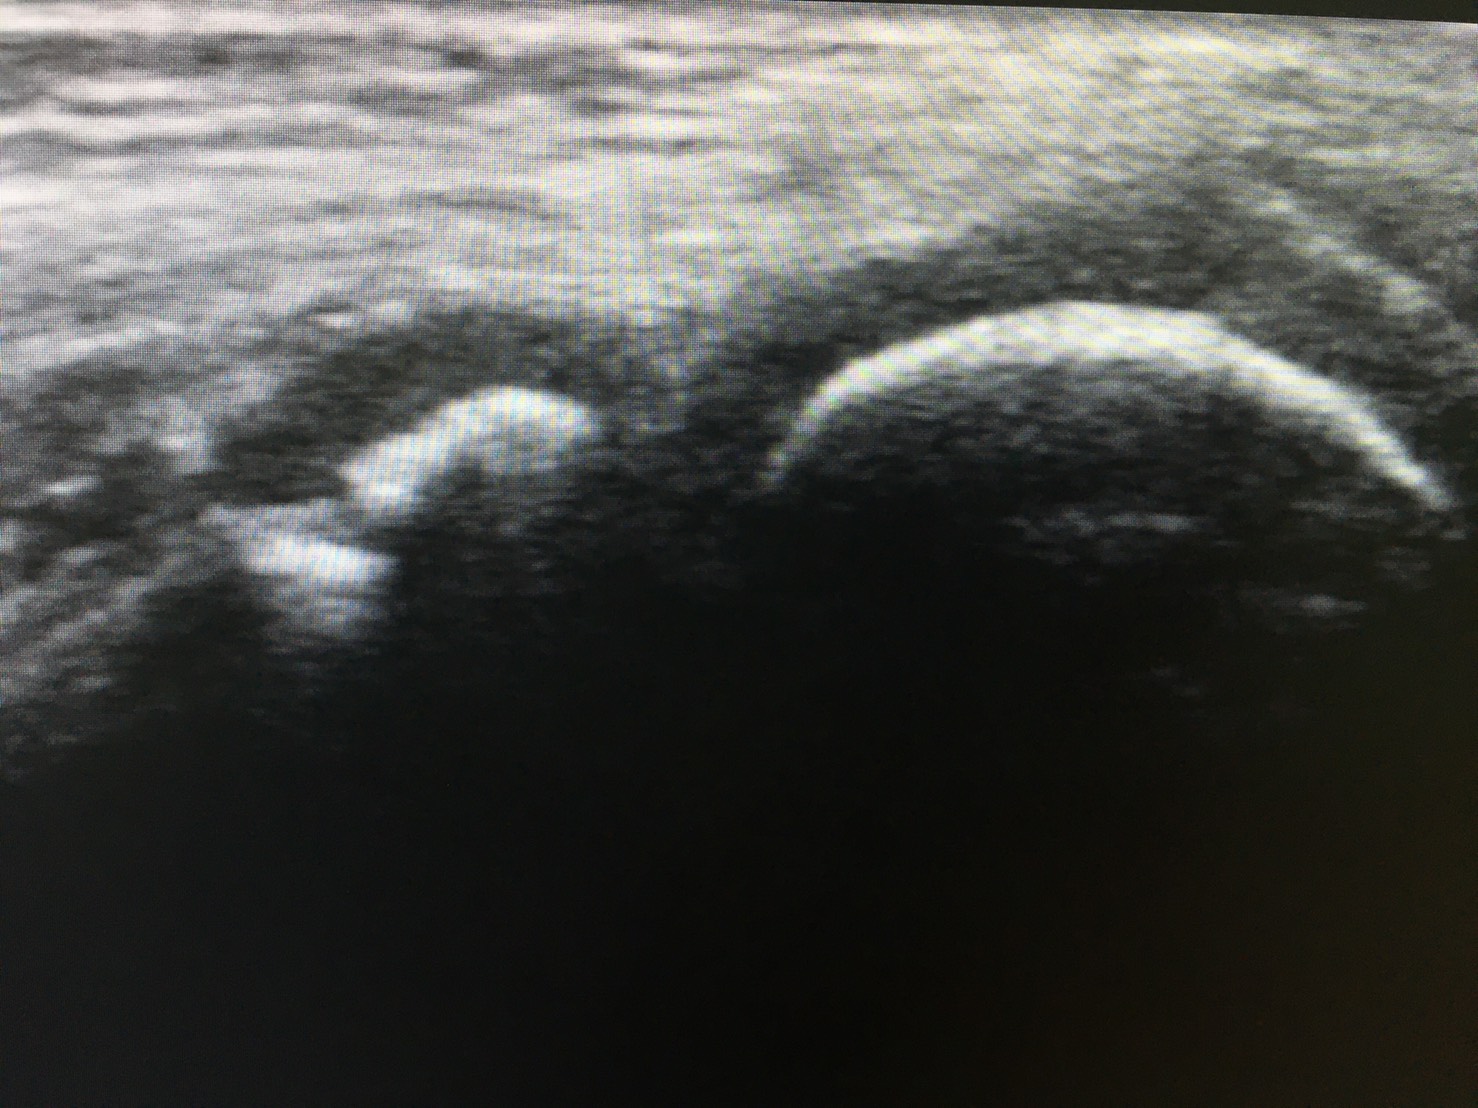

超音波検査は有用なツール

近年の超音波検査の機能は著しく向上しており、筋、関節包、滑膜、関節軟骨、軟骨下骨を明瞭に描出することができます。

超音波検査によって離断性骨軟骨炎を早期に発見できれば、保存的に治癒する可能性は高くなります。

(引用:肩と肘のスポーツ傷害より)